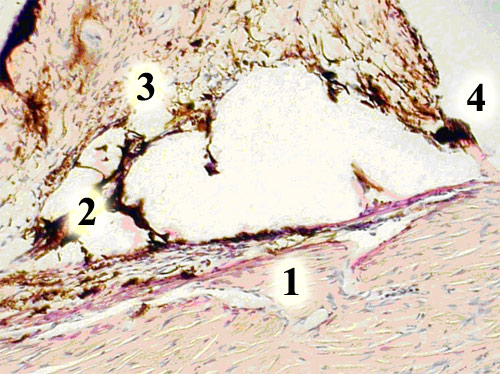

В группе кроликов № 1 вблизи фильтрационной зоны в радужке и цилиарном теле строение сосудов МЦР нарушено не было: артериолы имели диаметр от 50 до 100 мкм, стенка их тонкая, состояла из трех оболочек. Прекапилляры - диаметром 14-16 мкм, их эндотелий располагался над слоем мышечных клеток, эластическая мембрана отсутствовала, между эндотелиальными и мышечными клетками имелись перициты. Капилляры - диаметром 3-12 мкм, выстилка их представлена эндотелием, лежавшим на расщепленной базальной мембране. К ней примыкали перициты. В венулах - диаметром от 12 до 50 мкм -гладкомышечные клетки в стенке отсутствовали, она состояла из тонкого эндотелия и бо'льшего количества перицитов, чем в прекапиллярах, сходных с ними по диаметру. В более крупных венулах (50-100 мкм) средняя оболочка хорошо развита и была представлена гладкомышечными клетками. Общее количество сосудов 72,83±4,43, на долю артериол, прекапилляров, венул (АПВ) приходилось 20,00±1,13, здесь преобладали тонкостенные капилляры, которые в большом количестве расположены в цилиарных отростках (особенно в апикальных концах), задней части радужки. Просветы сосудов свободны, полнокровие их отсутствовало. Соединительная ткань слабо прокрашивалась альциановым синим в бирюзовый цвет, что говорило о незначительном содержании гликозаминогликанов, при ШИК-реакции наблюдались слабо окрашенные ШИК-положительные участки вокруг сосудов, где выявлялись гликопротеиды. Коллагеновые волокна в строме в незначительном количестве, аргирофильный каркас развит хорошо вокруг сосудов и в трабекулах. Эндотелий трабекул уплощенный, расположен ритмично по ходу щелей. Трабекулярный аппарат с четко прослеживавшимся каркасом корнеоувеальной и корнеомышечной части (рис. 1).

Рис. 1. Интактные кролики. Строение угла передней камеры глаза: 1 - шлеммов канал, 2 - корнеомышечная часть трабекулы, 3 - корнеоувеальная часть трабекулы, 4 - гребенчатая связка. Окраска гематоксилином и эозином. Ув.-180

Длина корнеоувеальной составляла 65,34±4,77 мкм, ее толщина по ходу к шлеммову каналу была равной 147,99±4,03 мкм. Фонтановы пространства, как корнеоувеальной, так и корнеомышечной части, округлой формы, равномерного диаметра и величины. Длина последней составляла 71,00±6,55 мкм, по толщине она равнялась 95,45±2,55 мкм. Две части трабекулы соединялись между собой гребенчатой связкой, длина которой 148,02±4,43 мкм. К трабекуле со стороны склеры примыкал венозный синус склеры (шлеммов канал), который был образован эндотелием, а стенкой его являлся коллагеновый каркас склеры. Просвет канала свободен, передняя его стенка отстояла от гребенчатой связки на 91,30±5,00 мкм, ширина просвета в срезах 73,32±2,52 мкм, высота - 23,52±1,15 мкм. Угол передней камеры широкий, в его тканях отсутствовали фиброз и отложение свободного пигмента в строме.